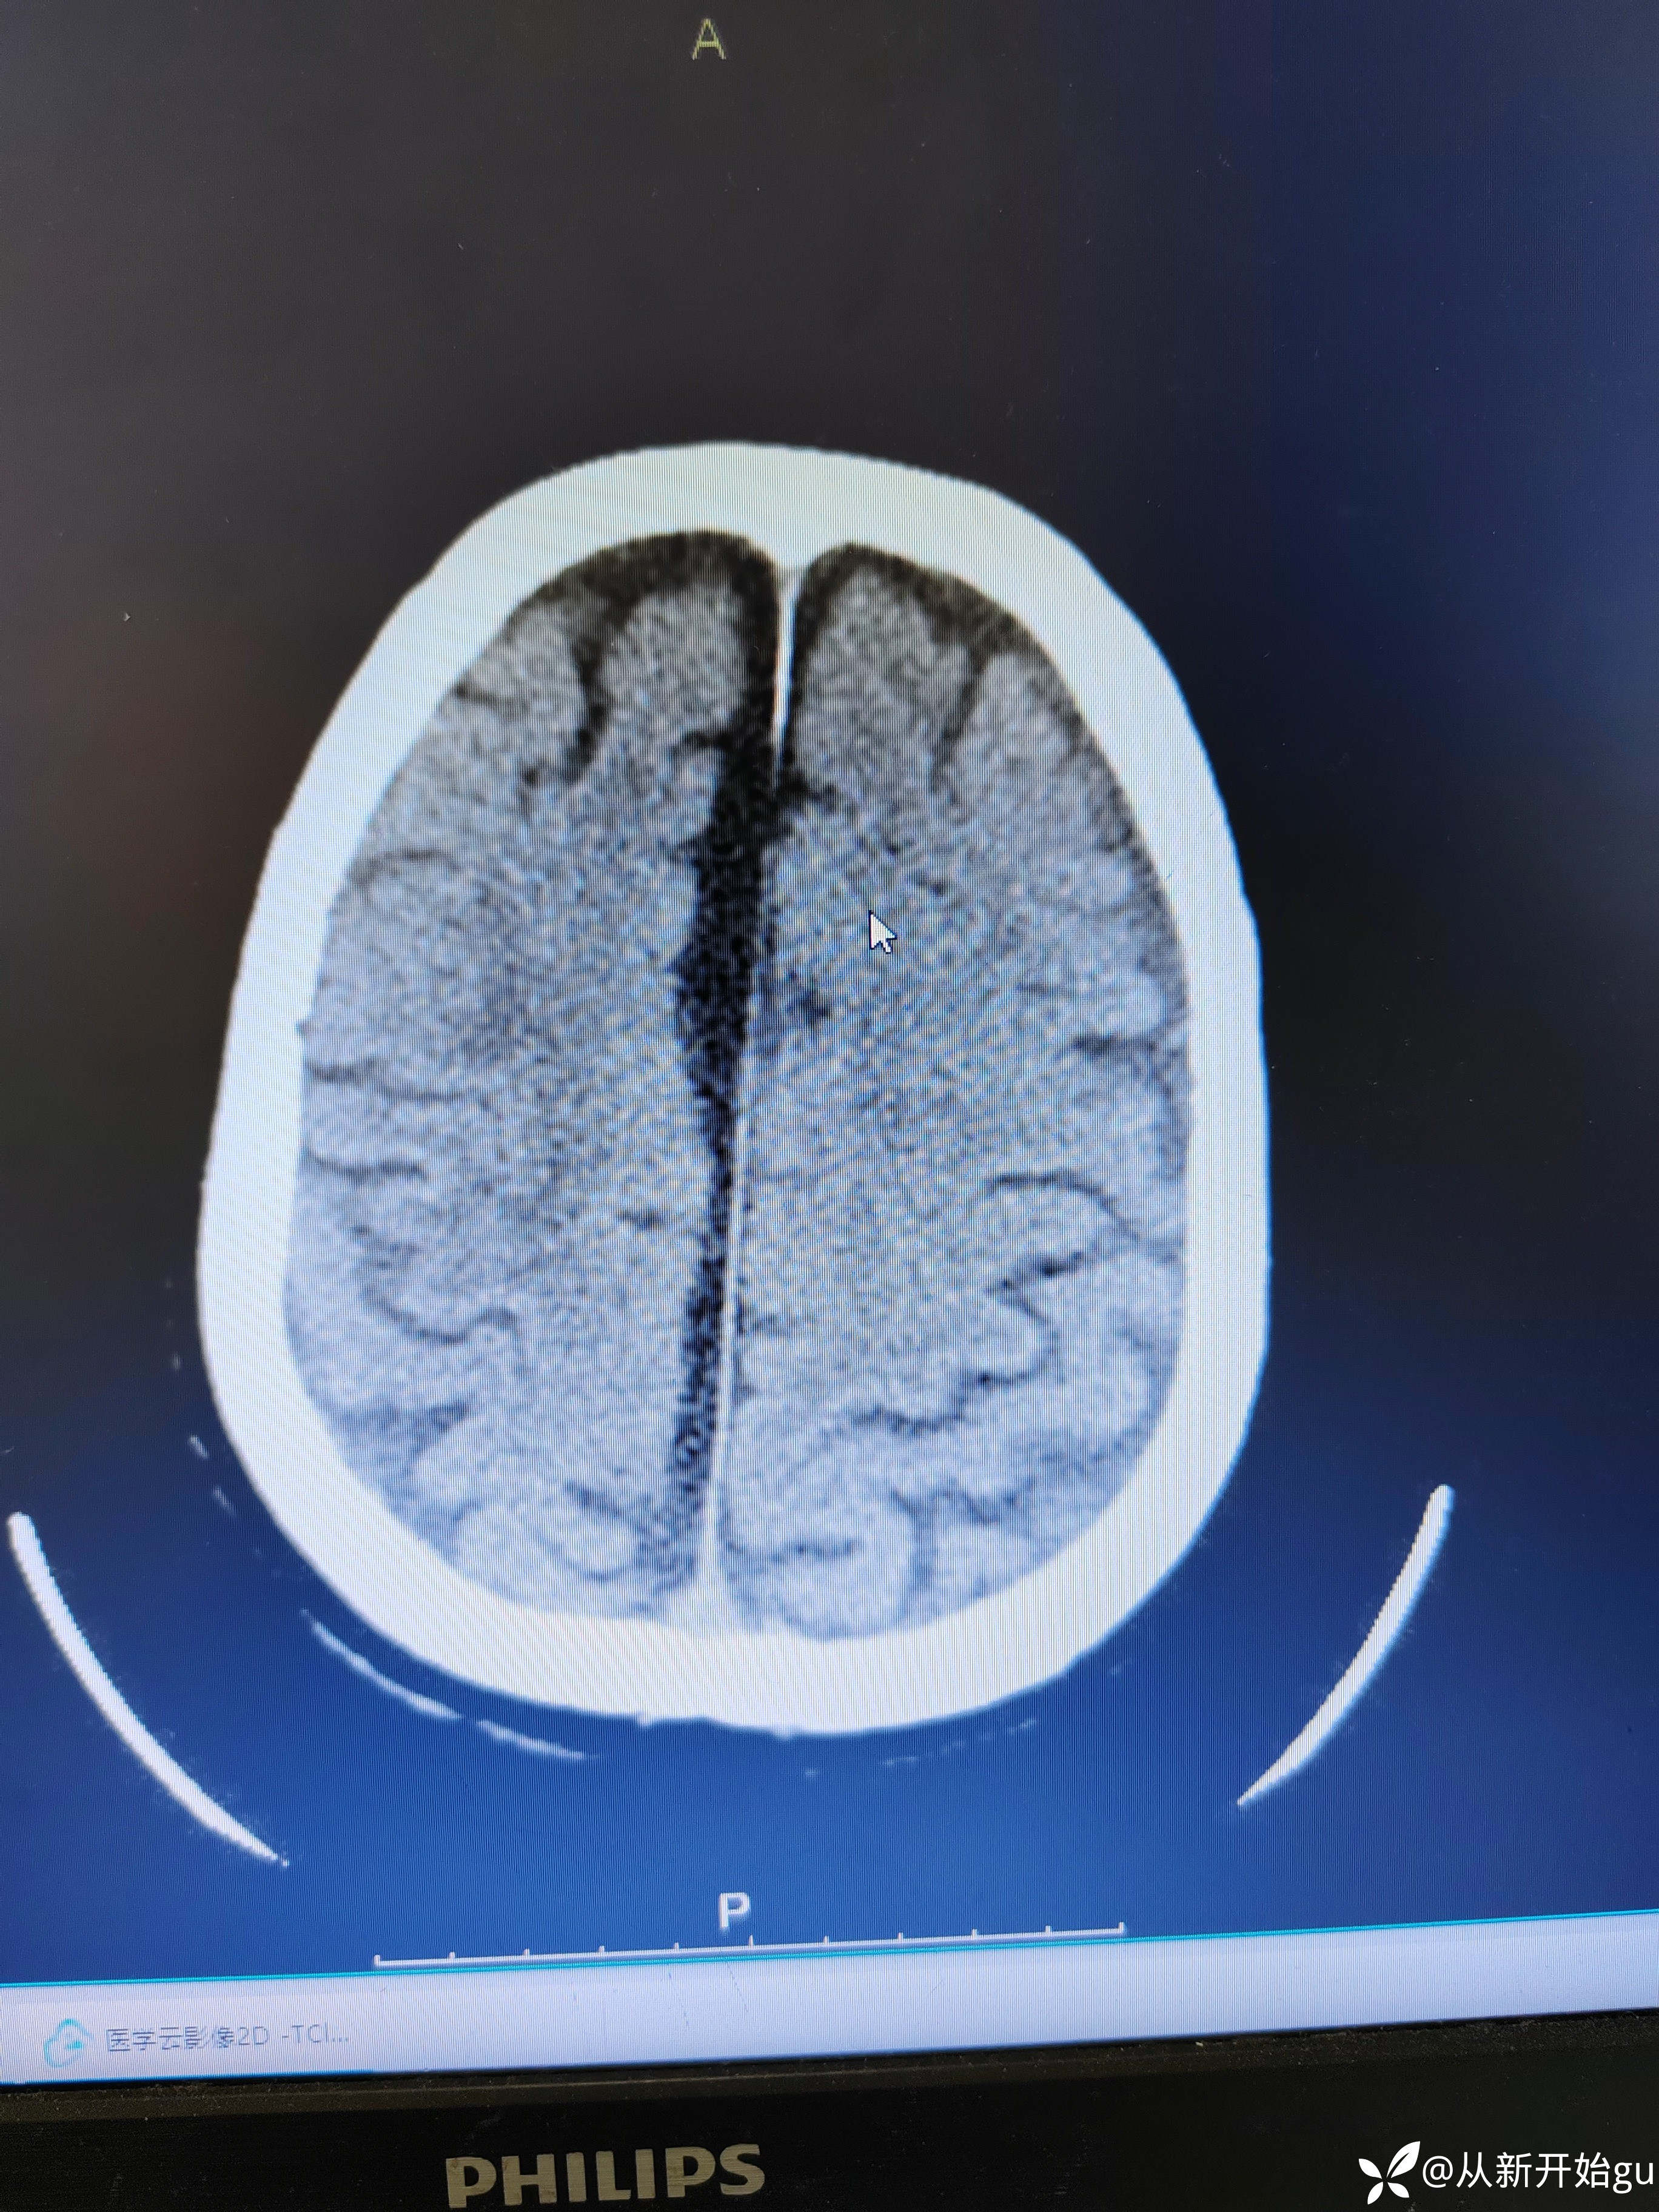

神经内外最近热帖已更新